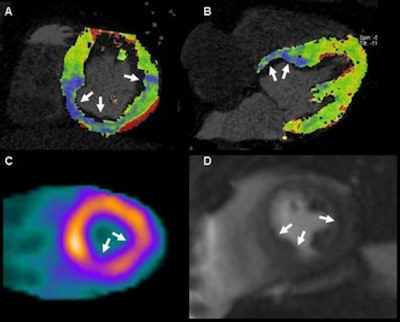

| In a 61-year-old man with suspected coronary artery disease, myocardial stress perfusion CT (a, b) reveals hypoperfused regions corresponding to SPECT (c) and MRI (d) studies. |